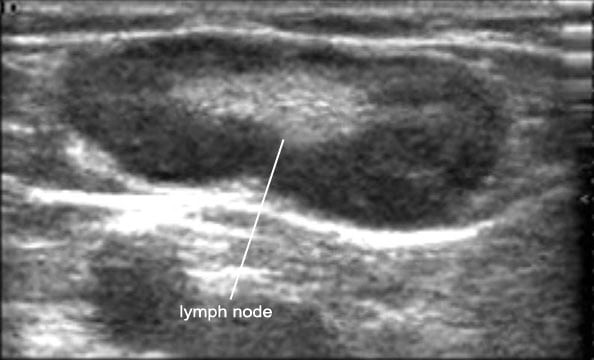

Мезентериальные лимфатические узлы: УЗИ и диагностика